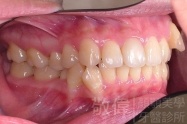

矯正前-右   矯正前-正   矯正前-左

矯正後-右   矯正後-正   矯正後-左

上顎暴牙且牙齒極度混亂,經由矯正之後,臉型大幅度改善,牙齒的排列更加的整齊健康。相較於之前眼神充滿精神,自信心展現無遺。